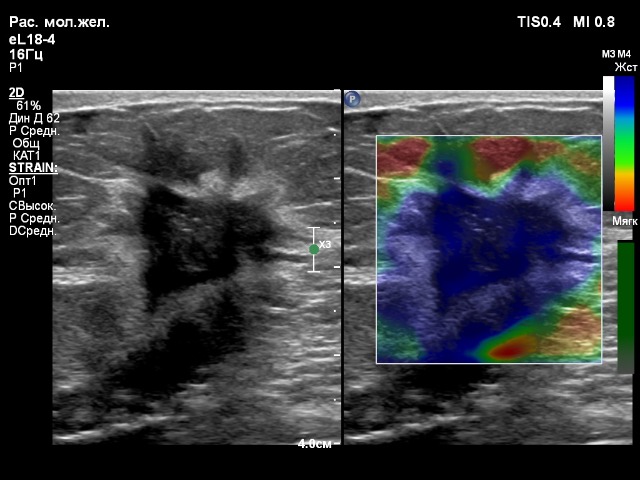

2. Датчик eL18-4

Если покупать один линейный датчик, то тогда это eL18-4.

Очень мне понравился. Он прекрасно работает и на низких частотах с достойной картинкой сосудов, и на высоких частотах (щитовидная, молочные железы, мягкие ткани). У аппарата 4 активных порта, 4 датчика - ничего не надо переставлять. Это очень удобно. И тут датчик eL18-4 выполняет свою работу на 100%.

По картинке больше всего понравился eL 18-4, оба случая. Но на вкус и цвет, как говорится)

Компрессионная эластография данного образования молочной железы на датчике eL18-4 получилась быстро и качественно, а на датчике L18-5 хуже получалась, индикатор качества не поднимался до верха, что указывало бы на высокое качество эластограммы, которую можно оценивать. На датчике eL18-4 можно сказать влёт.

Взлет не на датчике, а на эмоциях!Компрессионная эластография данного образования молочной железы на датчике eL18-4 получилась быстро и качественно, а на датчике L18-5 хуже получалась, индикатор качества не поднимался до верха, что указывало бы на высокое качество эластограммы, которую можно оценивать. На датчике eL18-4 можно сказать влёт.